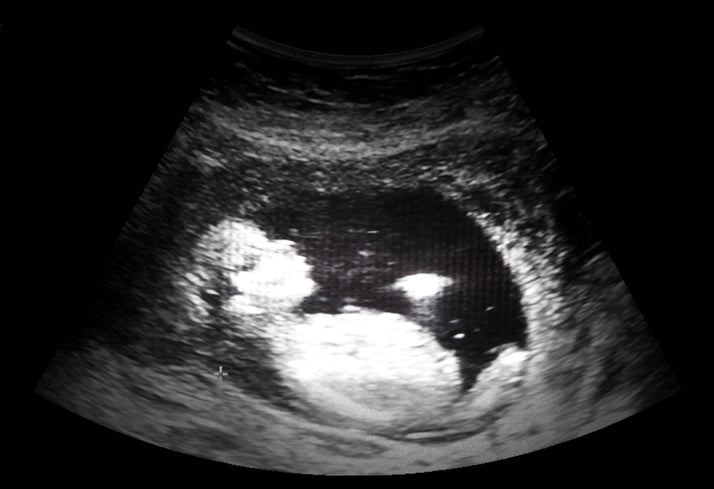

18 Week Fetus Yawns in Utero!

Look at this yawn!

But what else is happening in utero right now? Take a look at this 18-week ultrasound. You can clearly see the baby yawning wide, demonstrating the powerful muscles of the jaw that have developed. As your baby grows he will continue to swallow amniotic fluid and excrete urine, which he then swallows again, recycling the volume of amniotic fluid every few hours.

At 18-weeks gestation, an ultrasound is performed on the abdomen.

The baby is just under 6 inches long and weighs in around 6 ½ ounces.